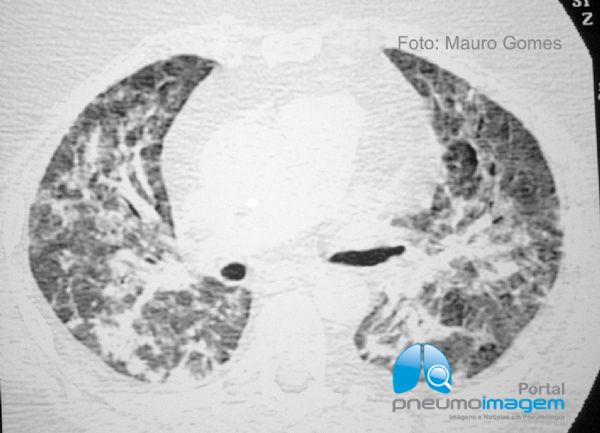

O tratamento recomendado para a pneumonia aguda por CMV é ganciclovir, droga que previne a replicação do DNA viral pela inibição da enzima DNA polimerase. Esse corte tomográfico, assim como os próximos dois, são do mesmo caso após o tratamento com ganciclovir. Imunoglobulina intravenosa em altas doses pode ser empregada em associação ao ganciclovir. Como profilaxia da infecção por CMV nos transplantados, recomenda-se aciclovir ou ganciclovir antes e depois do transplante.

The recommended treatment for acute CMV pneumonia is ganciclovir, a drug that prevents viral DNA replication by inhibiting the DNA polymerase enzyme. This image is after the treatment with ganciclovir. High dose intravenous immunoglobulin may be used in combination with ganciclovir. As a prophylaxis of CMV infection in transplant recipients, acyclovir or ganciclovir is recommended before and after transplantation.

A sequência das últimas três imagens são do mesmo caso após o tratamento com ganciclovir.

The sequence of the last three images are the same case after ganciclovir treatment.